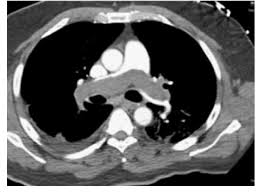

Rapid is called for a 62-year-old man in shock. He is hypotensive on vasopressors, hypoxic despite 100% FiO₂, and CTA chest is shown below. He was admitted under Neuro ICU initially for intracranial surgery for glioma removal. This is the recommended definitive therapy for this patient:

Catheter-directed thrombectomy (mechanical or aspiration thrombectomy)